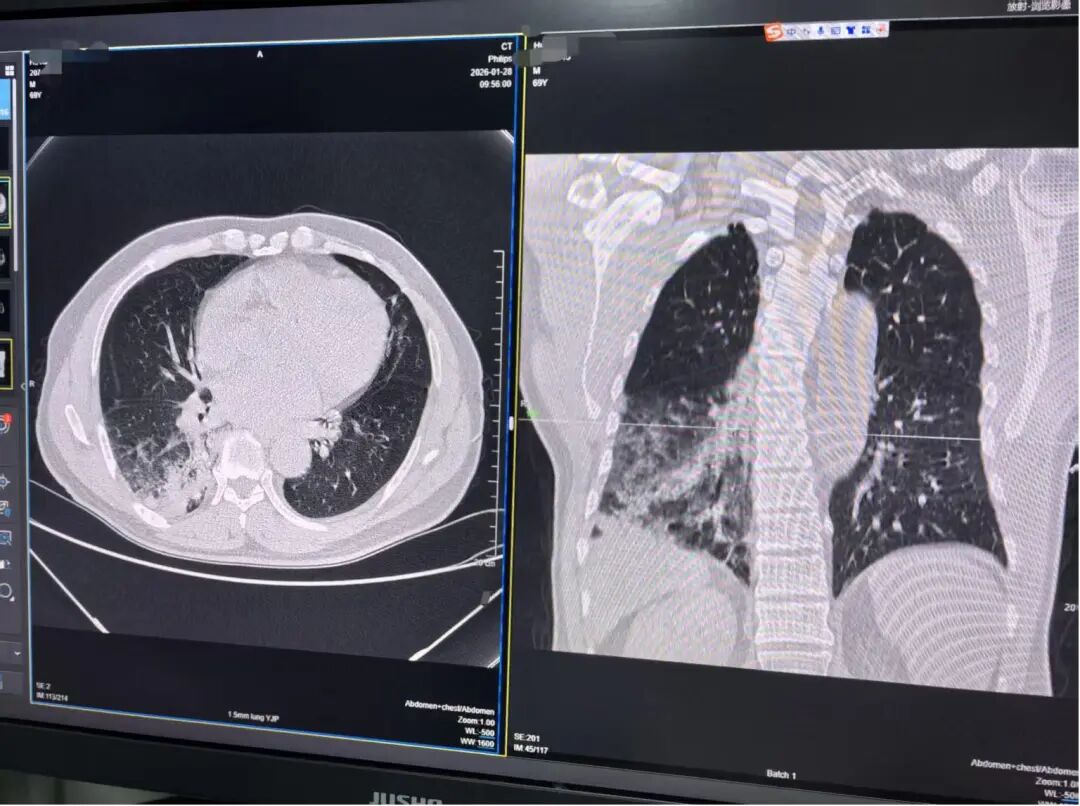

胡爷爷的肺部CT结果

2月3日,记者在湖南中医药大学第一附属医院见到了即将出院的胡爷爷。据胡爷爷女儿讲述,69岁的胡爷爷在自家小院养了二十几只鸡鸭,一天突然感觉到乏力、畏寒,老人以为自己得了感冒,于是在当地门诊以感冒治疗,没想到6天后,不适感没有缓解,还高烧至38.4℃,出现了发热难退的症状。到当地医院检查后,CT结果提示“肺部感染”,于是转院至湖南中医药大学第一附属医院住院治疗。

据该院老年病科副主任医师陈亚介绍,胡爷爷入院当天体温高达39.8℃,连续用药后仍高热不退,因胡爷爷有家禽接触史,加上科室连续接诊了两例鹦鹉热,于是立即完善相关检查,最终经过诊断,胡爷爷确诊鹦鹉热衣原体感染。